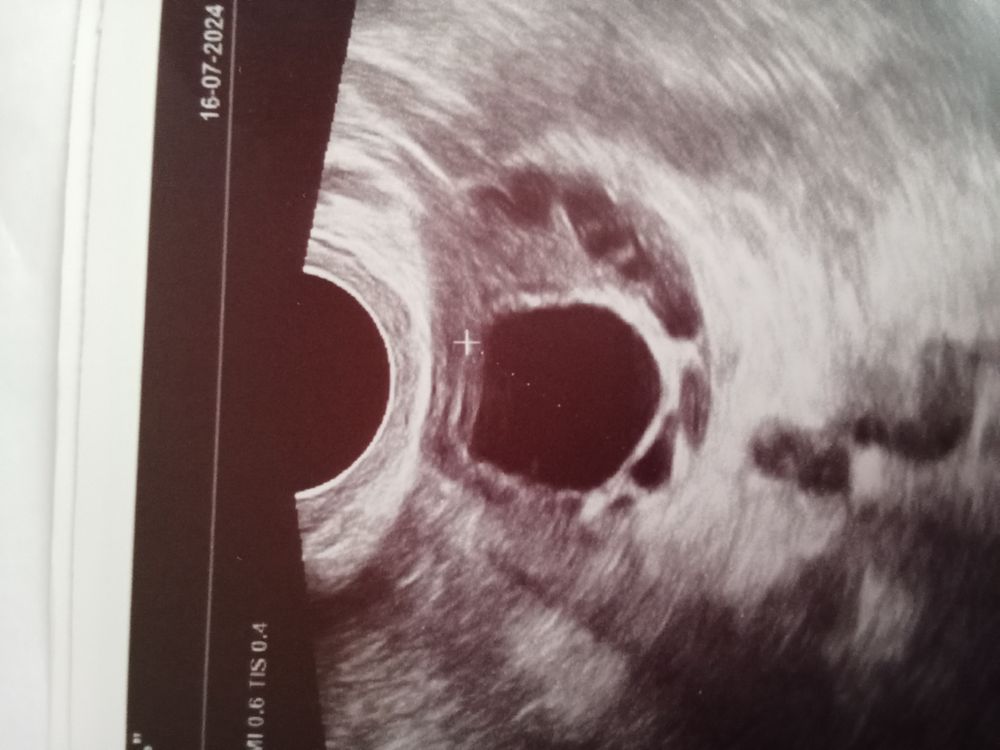

Решила этот цикл тестами ловить, хотя и так чувствую овуляцию, уж очень она болезненная. И на 17 ДЦ тесты показали пик, оранжевый тест. Но я острой боли не почувствовала, просто сильная, ноющая. Пошла сегодня на УЗИ, а сегодня 19 ДЦ и вуаля, нет овуляции, только доминант

Но самое главное я увидела яйценосный бугорок, тест зелёный сегодня, жду пик, и свою овуляцию. Кто разбирается в УЗИ, нормальный эндометрий? На вид как с пятнами😁😁😁, он как обычно за день до о уже 11.5 мм